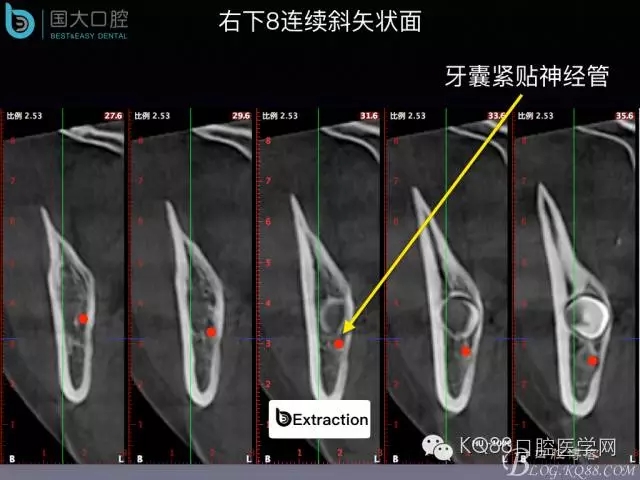

阻生牙的預(yù)防性拔除